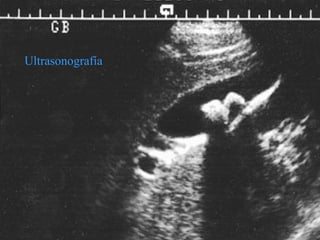

Ultrasonografía